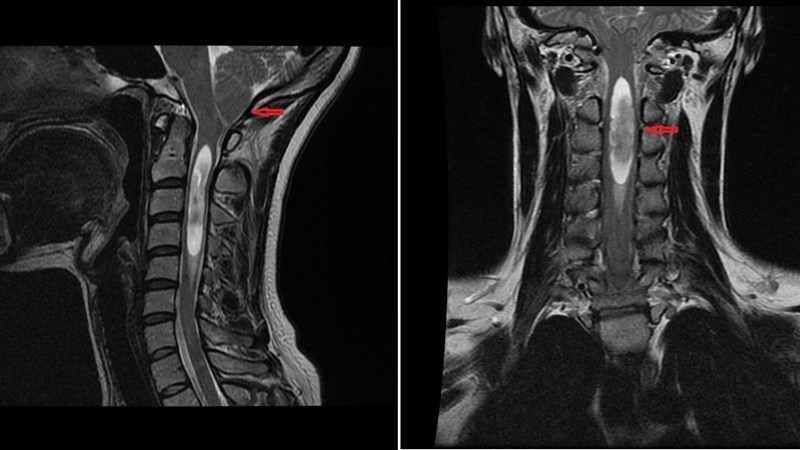

| Магнитно-резонансная томография (МРТ) | Визуализация очагов демиелинизации (бляшек) в головном и спинном мозге. Часто используется контрастное вещество для выявления активных, воспалительных очагов. | Неинвазивная и безболезненная процедура. Ребенку нужно будет лежать неподвижно в аппарате МРТ. Маленьким детям может потребоваться седация. |